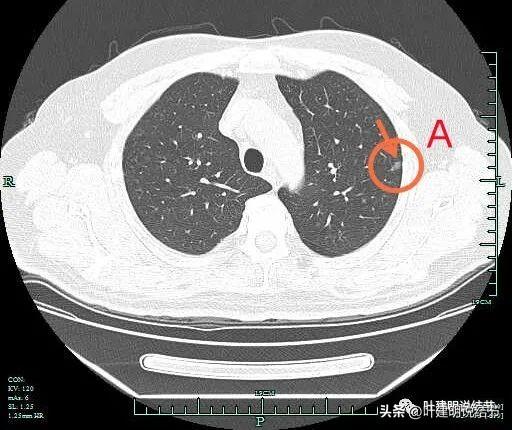

1、适当使用图片和图表来辅助说明文章内容,提高读者的阅读体验,在介绍骨水泥手术原理和过程时,可以插入相关图片或示意图。